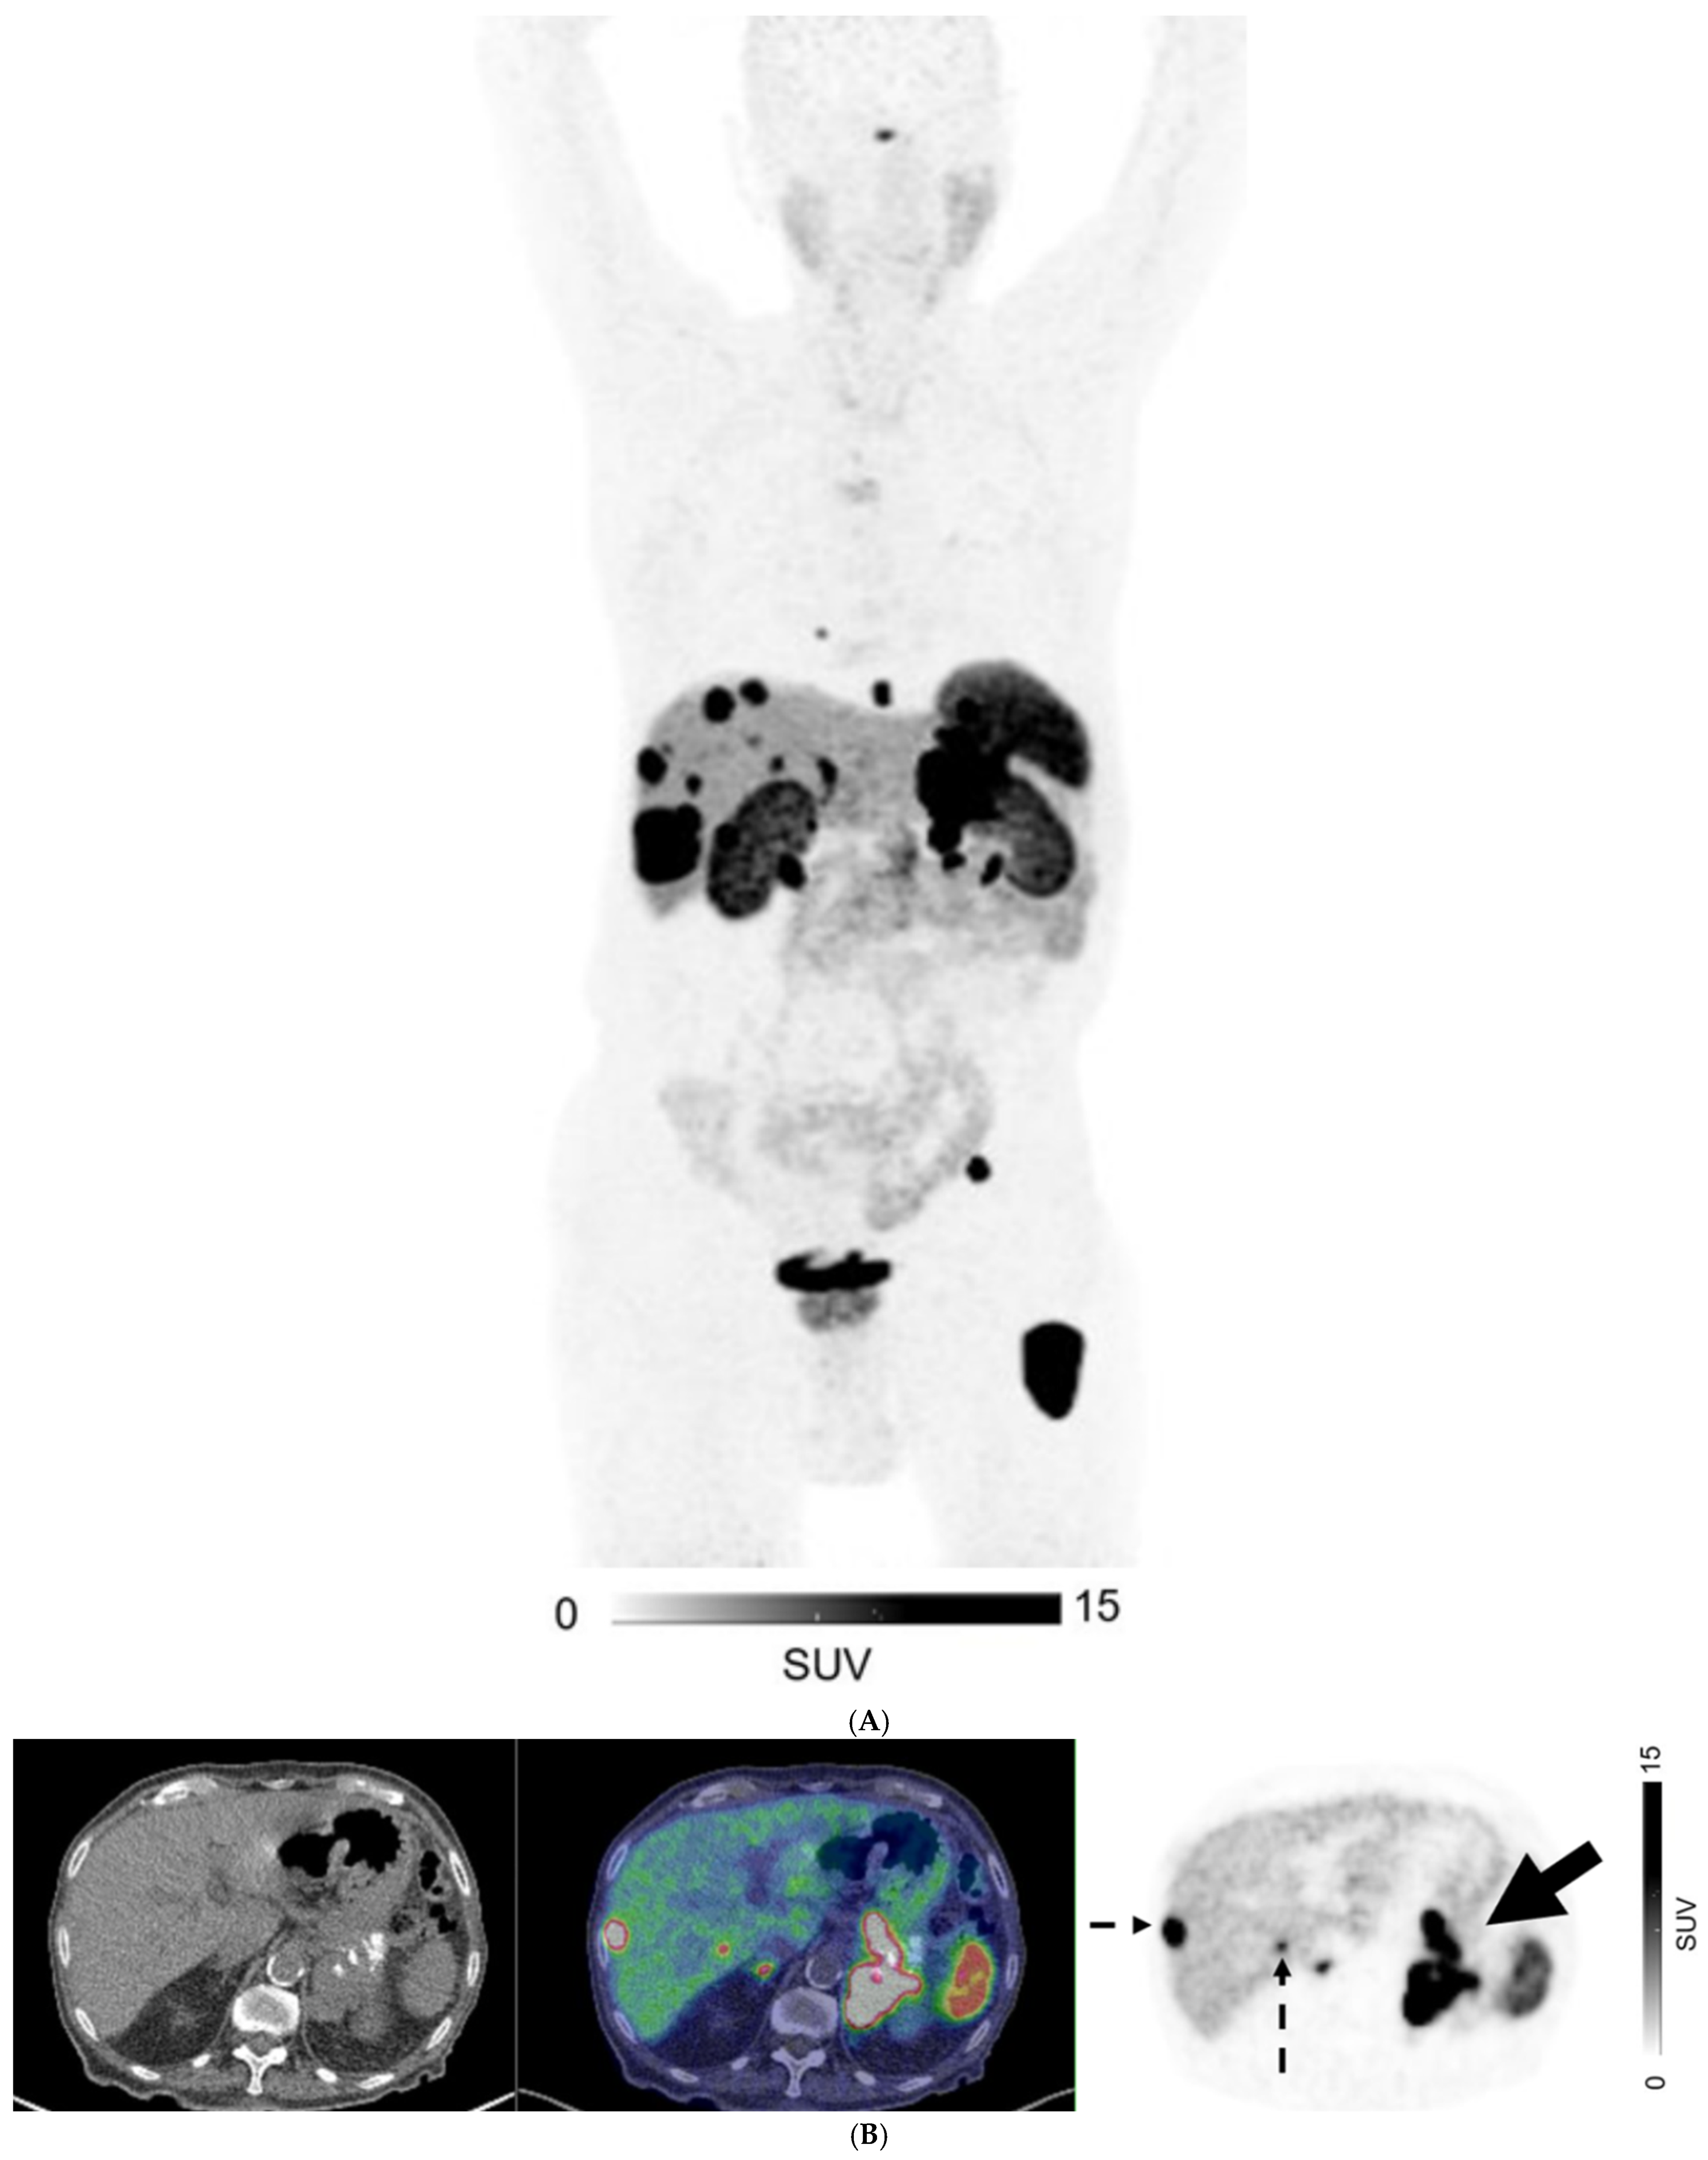

Figure 4.

A 40-year-old man with metastatic well-differentiated G3 neuroendocrine tumor, unknown primary. Contrast-enhanced CT ((A) Axial image) shows multiple liver deposits (histologically proven; solid arrows) and lytic bone lesion at T12 vertebral body (dotted arrow). 68Ga-DOTATATE PET/CT ((B) Fused axial PET/CT image left and Axial PET image right) show no corresponding focal radiotracer uptake.